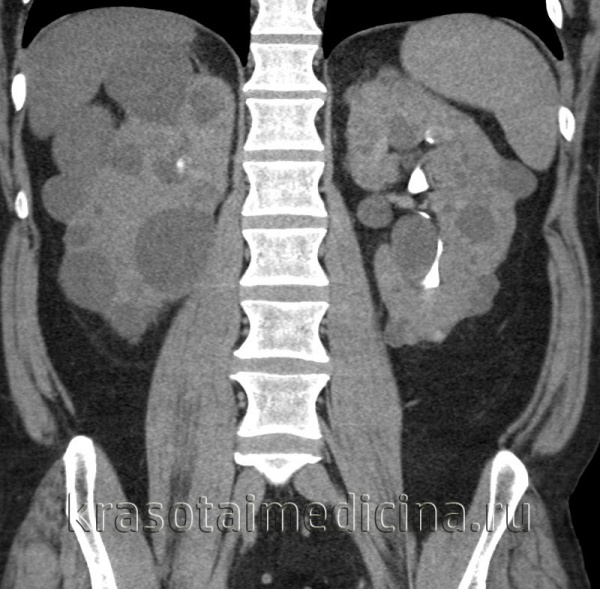

При УЗИ почки резко увеличены, но форма их сохранена. Паренхима имеет повышенную эхогенность, крупнозернистая, с наличием мелких эхонегативных зон («соль с перцем»). На более поздней стадии помимо веретенообразных могут появиться кисты сферической формы. УЗИ печени выявляет повышенную эхогенность, а позднее — хорошо различимые кисты желчных протоков.

Диагностике помогают данные КТ и МРТ почек и печени и экскреторной урографии.

При МРТ собирательные трубочки расширены в виде веретенообразных, радиально расположенных кист, но решающего значения при постановке диагноза эти данные не имеют. В кисты превращены от 10 до 90% собирательных трубочек — в зависимости от тяжести и возраста начала заболевания. При биопсии печени находят разрастание желчных протоков, портальный и перипортальный фиброз.

Патоморфология аутосомно-рецессивного поликистоза почек. Обе почки резко увеличены, содержат много кист в корковом и мозговом веществе. Под микроскопом видны многочисленные кисты, распространяющиеся от мозгового вещества в корковое и расположенные преимущественно в собирательных трубочках и протоках. У плодов наблюдаются преходящие кисты и в проксимальных канальцах. Прогрессирующий фиброз интерстициальной ткани и атрофия канальцев в конце концов приводят к почечной недостаточности.

Диагностика аутосомно-рецессивного поликистоза почек. Пальпируемое двустороннее объемное образования в боковых отделах живота у грудного ребенка с гипоплазией легких, маловодием и артериальной гипертонией в отсутствие поликистоза почек у родителей позволяет диагностировать болезнь. При УЗИ почки обычно резко увеличены и равномерно повышена их эхогенность со стертостью границы между корковым и мозговым веществом. Диагноз подтверждают также клинические и лабораторные признаки фиброза печени, патологические изменения желчных протоков в биоптате печени, наличие поликистоза почек у сиблингов или близкое родство родителей. Аутосомно-рецессивный поликистоз почек следует отличать от увеличения почек при поликистозной дисплазии, гидронефроза, опухоли Вильмса и двустороннем тромбозе почечных вен. В семьях хотя бы с одним больным ребенком возможна пренатальная диагностика с помощью анализа генетического сцепления и использования информативных маркеров.